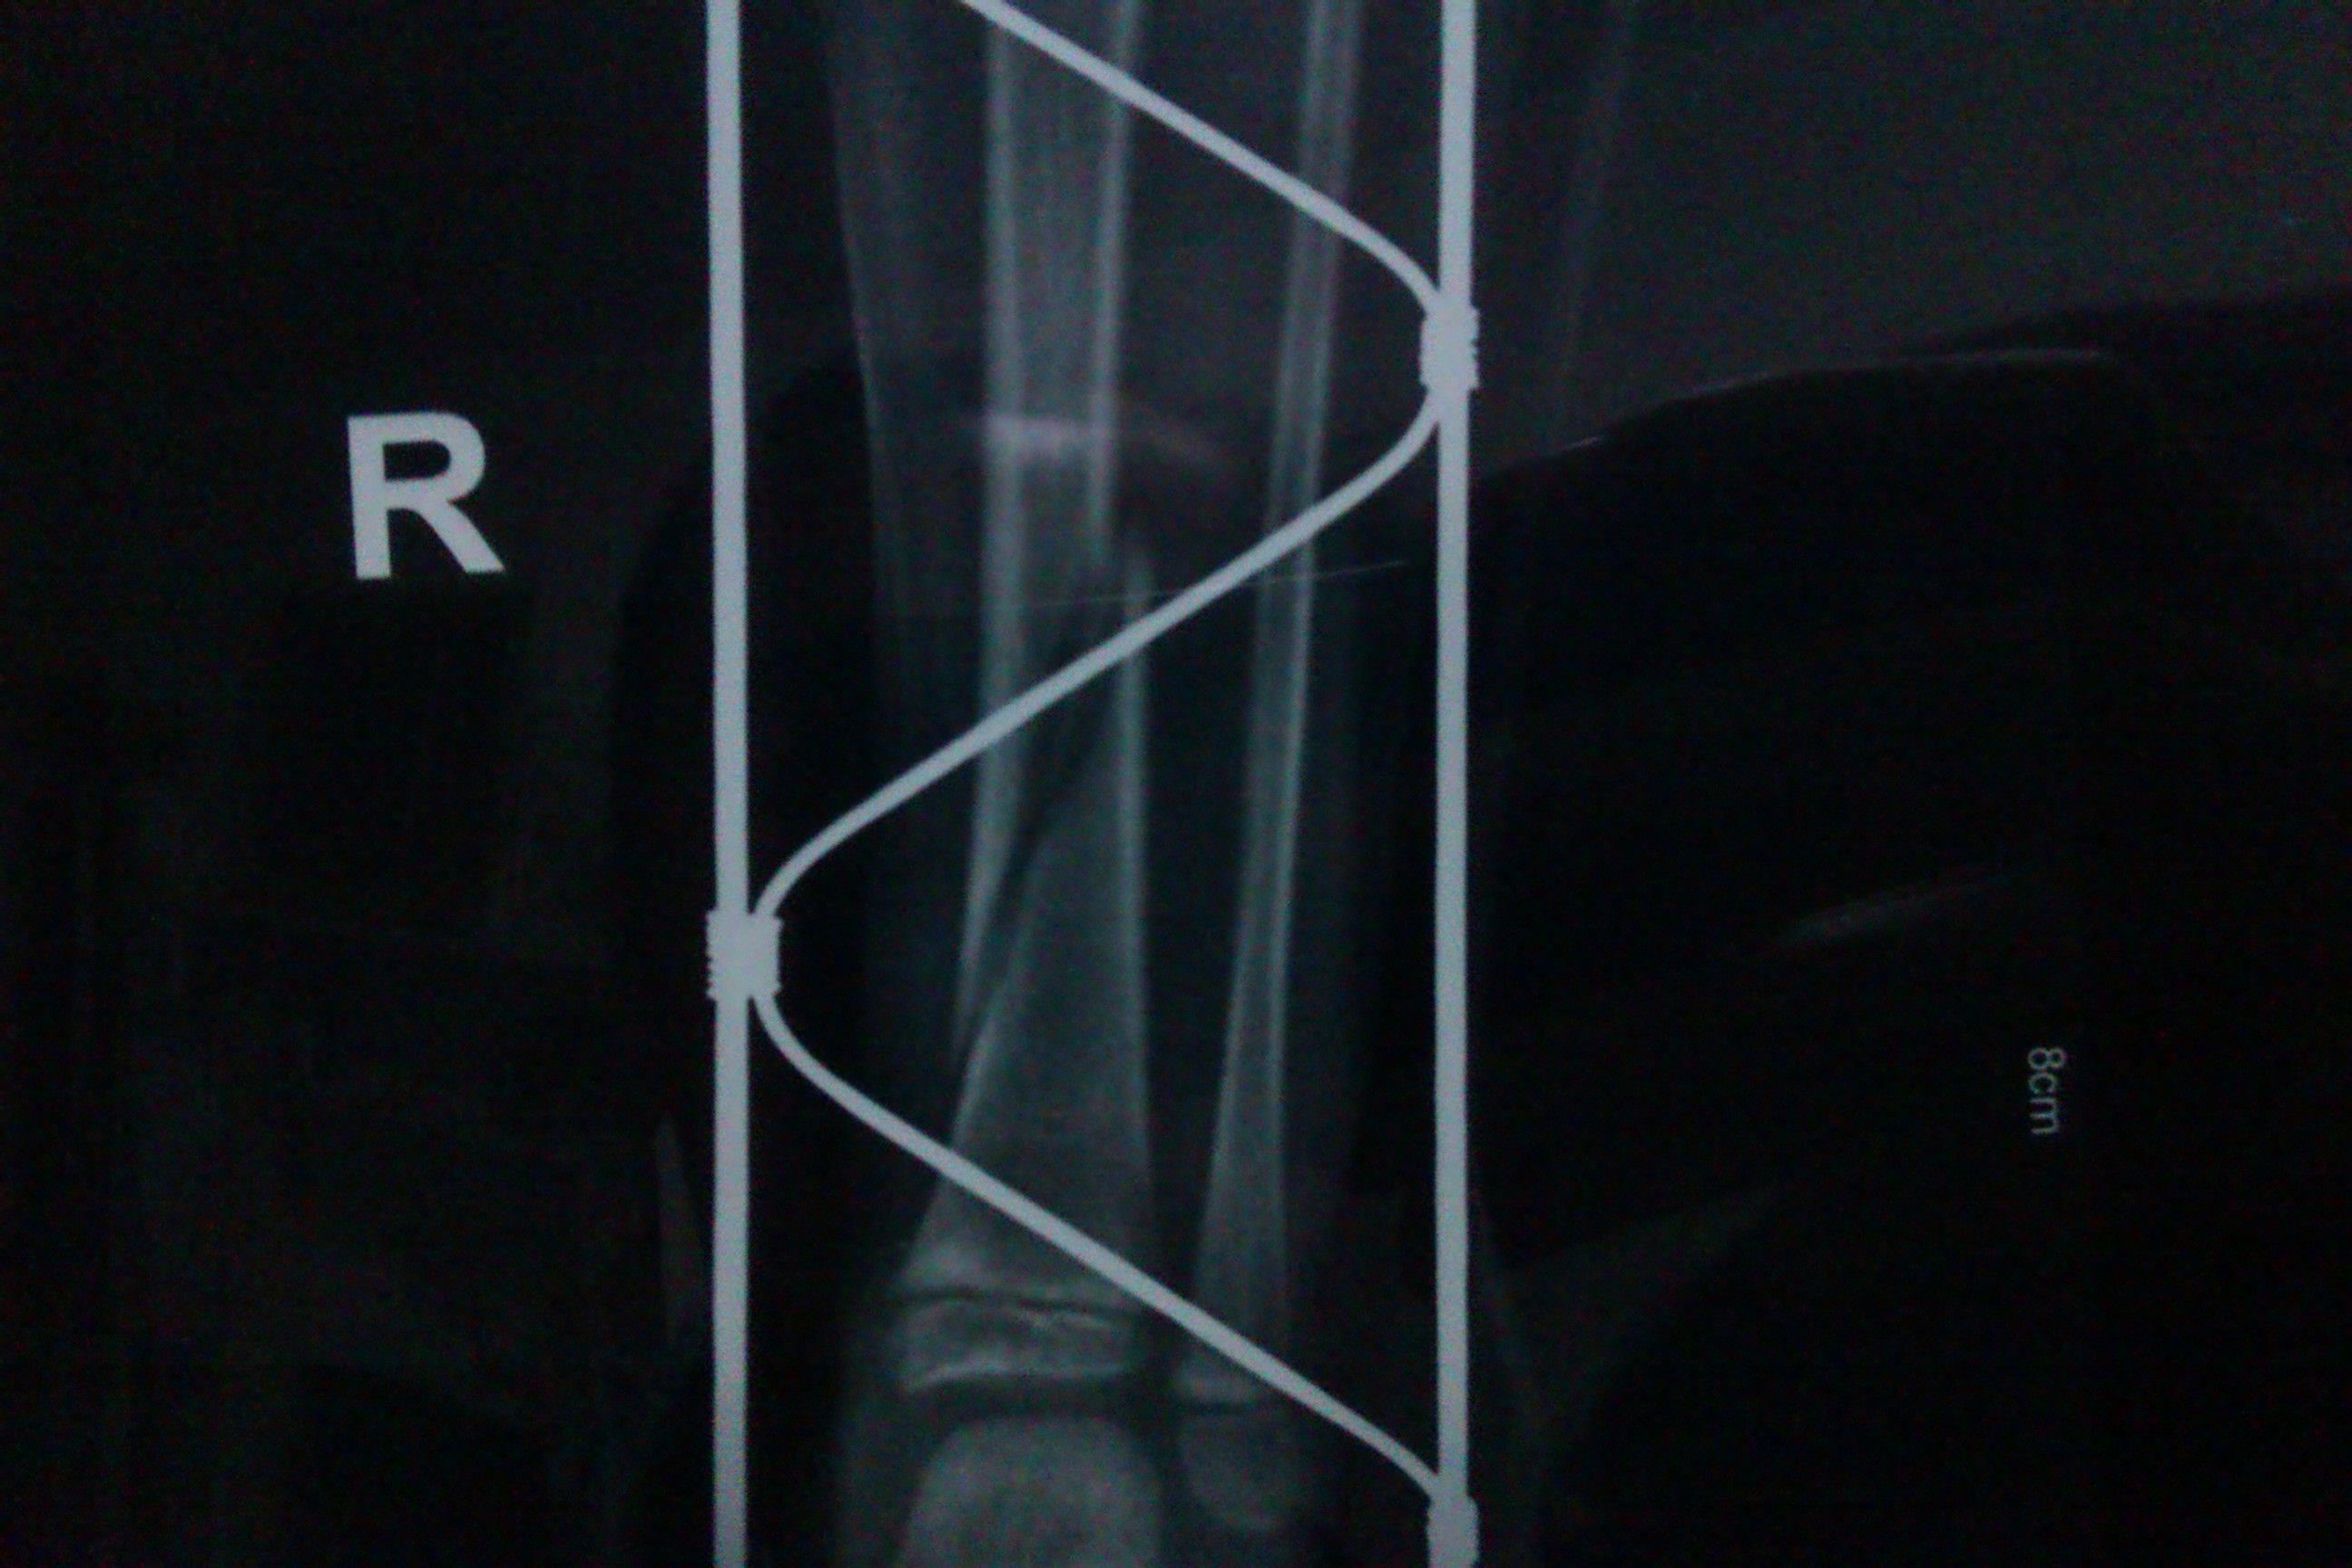

4岁幼儿螺旋形骨折10天后发现位移,家长心急如焚

2013年10月9日发生骨折,拍片确认为螺旋形骨折,采用手法复位,上夹板固定,10月17日复查发现对位偏差,医生任然采用手法复位,夹板固定。 希望得到医生的帮助:请问现在距离受伤时已经近10天了,继续采用手法复位和夹板固定能纠正对位的偏差吗?会留下残疾吗?我们应该如何采取治疗措施呢?

根据你的片遮抽子来看,属于胫骨下段骨折,本来下段骨折就很不稳定,不知道你第一次片子的情况,应该对比下骨折的位置和形态,是否有加重等情况。目前来看,骨折端缝某航以隙明显,也有愈合的可能,且会塑形,只是固定时间比较长,且要可靠,护理比较重要,避免下地受力负重等,同时限制了小朋友的日常活动,其中利弊你们自己权衡利弊咯,建议至专业有经验的骨科医院随诊。立侨